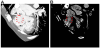

A 34-year-old woman visited our outpatient clinic due to dyspnea and chest discomfort newly developed one month ago. The symptoms progressively worsened during a several months’ period. Dyspnea was aggravated by exertion. Substernal chest pain was intermittent and of squeezing nature and it was not related to exercise. She had been heard about a hole between cardiac chambers when she was young; however, she did not remember the correct diagnosis. She had no other significant prior medical history except scoliosis. She was not a smoker and had no family history of heart disease. On initial examination, her general condition was good with blood pressure of 120/50 mmHg, and pulse rate of 77 per minute. She was afebrile, and there was no jugular venous distension or peripheral edema. There was a loud continuous murmur along with the left parasternal border line accompanied by a thrill. There were no other remarkable findings in chest and heart examinations. Electrocardiogram (ECG) showed nonspecific ST-T segment changes with normal axis (Figure 1A). Chest X-ray showed mild cardiomegaly and curved thoracic vertebrae (Figure 1B). There were no specific findings in blood tests including cardiac enzyme, inflammatory markers, rapid plasma regain test for syphilis and human immunodeficiency virus test. Transthoracic echocardiography (TTE) revealed normal size and function of both left and right ventricles (LV and RV). Color flow and pulsed wave Doppler identified a jet flow from the aorta to RV, at the level of the aortic root, seen during both systole and diastole (Figure 2 and Videos 1 and 2). There was no valvular stenosis or regurgitation of the aortic valve (AV). Rupture of SVA was suspected. However, the aneurysmal sac was not clearly defined by TTE, and other cause of intra-cardiac shunting, such as ventricular septal defect (VSD), could not be ruled out. Therefore, ECG-gated computed tomographic (CT) coronary angiography was performed to obtain information on additional cardiac pathology and relation to the coronary arteries. CT scan revealed a ring-like structure originating from the right coronary sinus of AV protruding to the RV. The ostium of the right coronary artery was not involved by the aneurysm, and there was no significant stenosis of coronary arteries (Figure 3A). Extravasation of the radiocontrast agent from the SVA to the RV was also seen on CT scan (Figure 3B). Based on these findings, the patient was scheduled for surgery. Immediately before surgery, transesophageal echocardiography (TEE) was carried out for surgical planning. The findings of TEE were concordant with those of aforementioned cardiac CT. TEE revealed a protruding aneurysmal sac with shunting from the right coronary sinus to RV (Figure 4 and Video 3). Invasive cardiac catheterization was not performed. Surgical findings confirmed a large aneurysm with a defect at right coronary sinus of the AV. There was no other combined cardiac pathology. Resection of the aneurysmal sac and repair of the aortic root using an autologous pericardial patch was performed. After surgery, TTE no longer showed abnormal shunt flow at the aortic root except minimal valvular regurgitation of the AV (Figure 5 and Video 4). She has been doing well without chest symptoms after surgery.